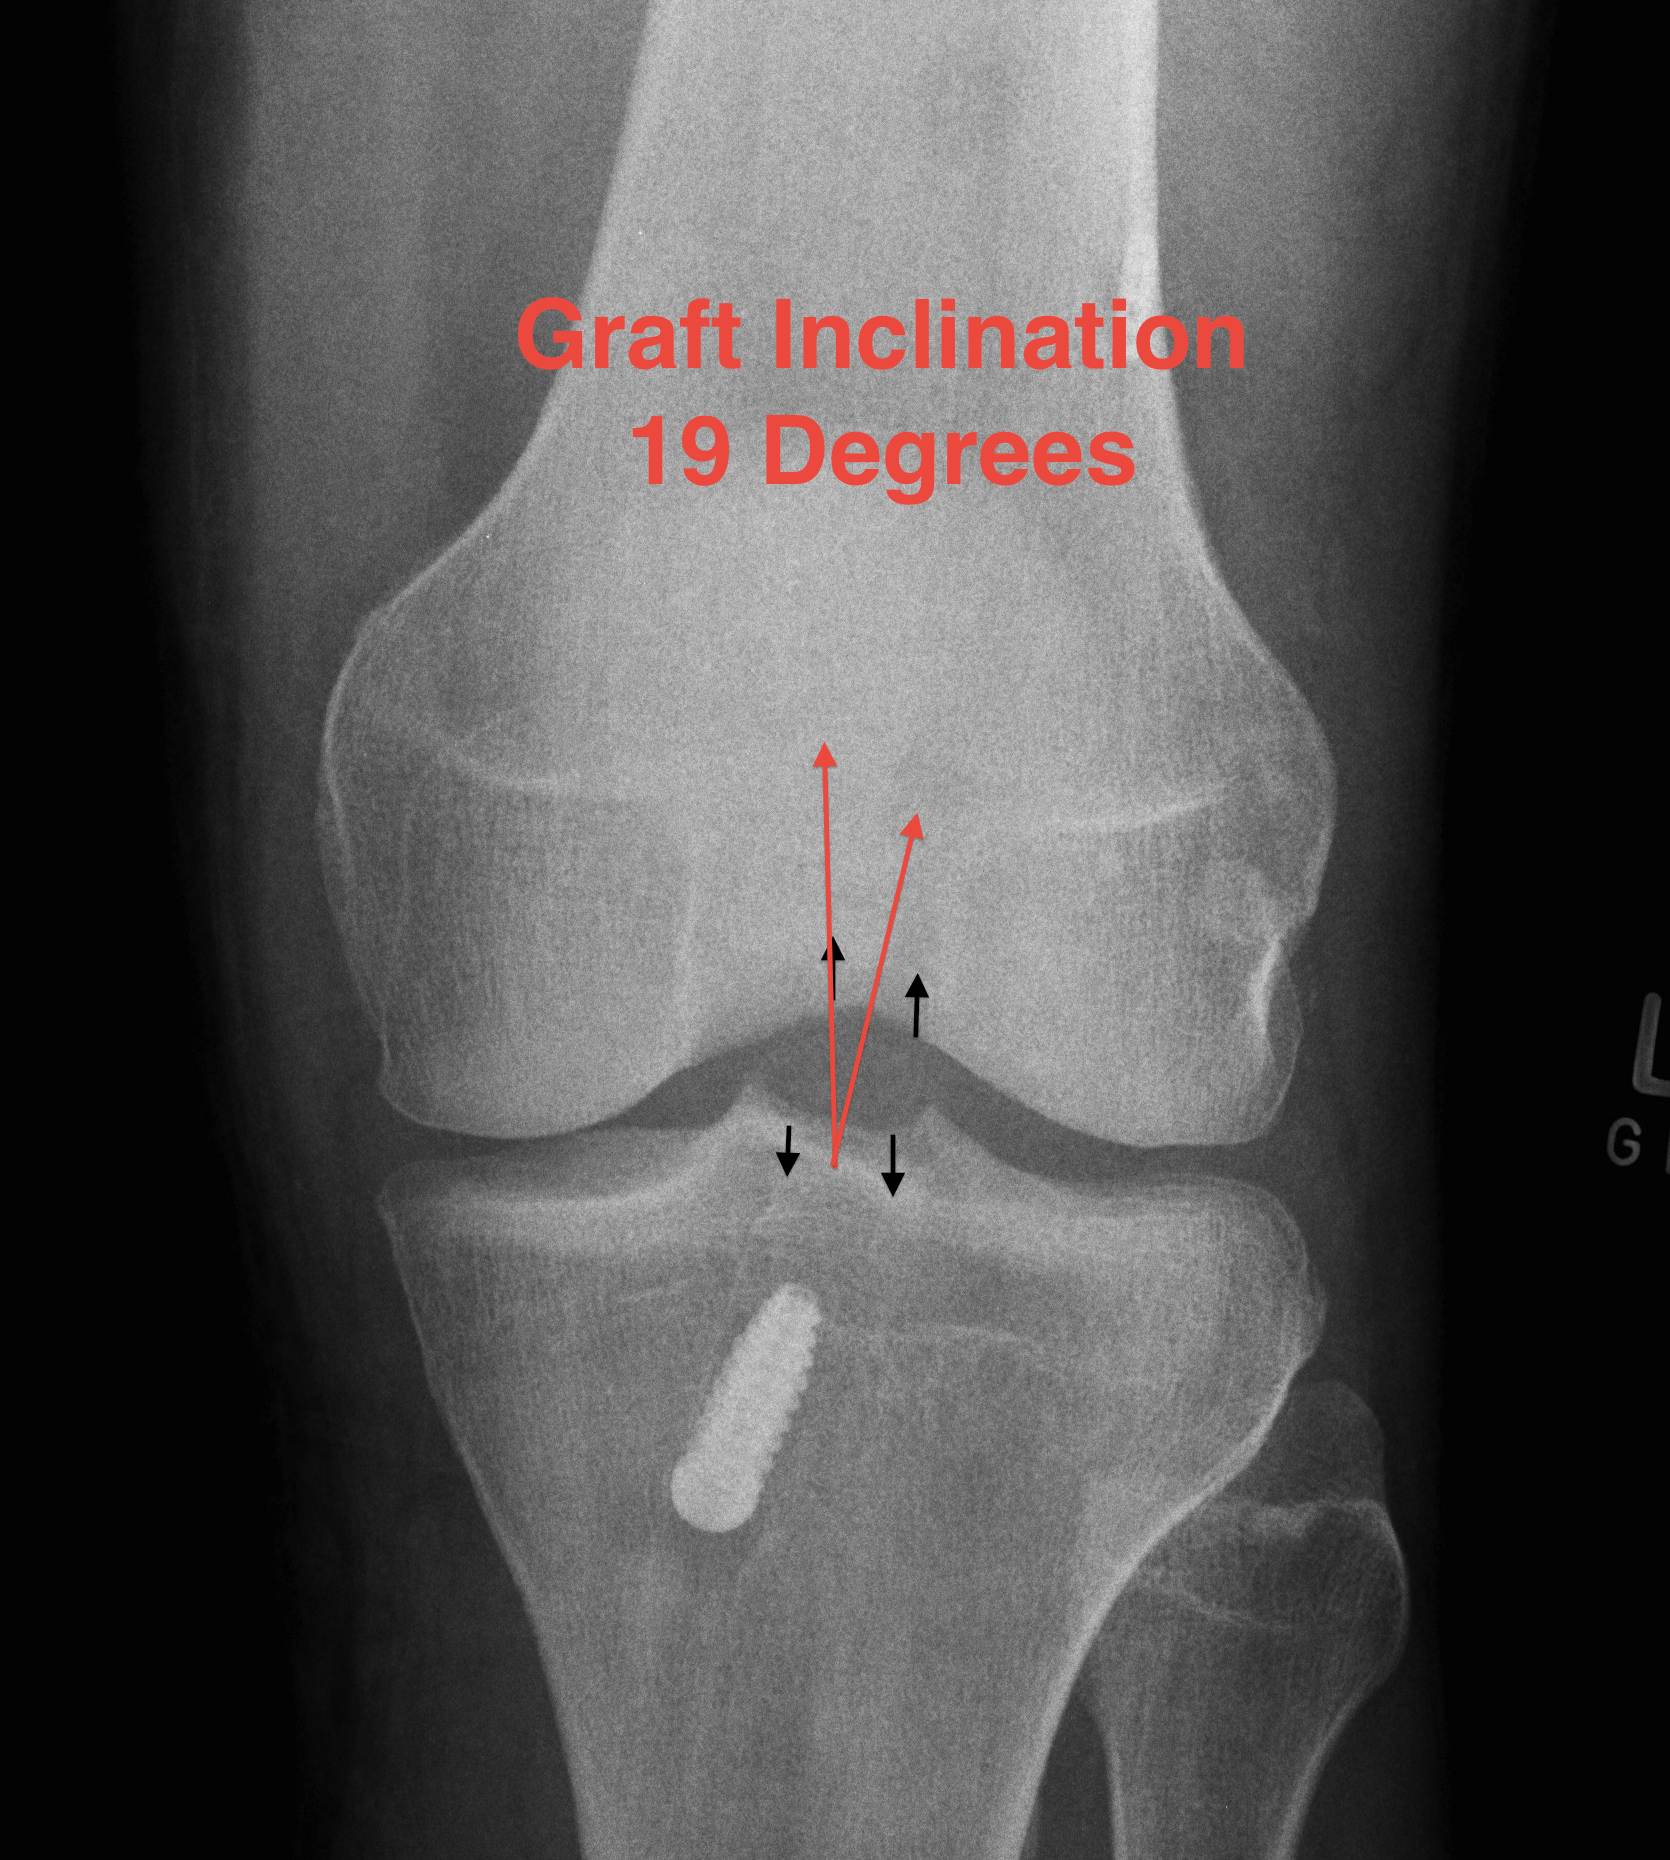

AP Xray

3. Graft inclination

- 19o

Good rotational stability

- 19o inclination in coronal plane

- avoid too vertical orientation

C. Vertical Graft

Fu etal Arthroscopy 2003

- cadaver study of graft in 10 v 11 o'clock position

- demonstrated increased rotational instability in 11 o'clock